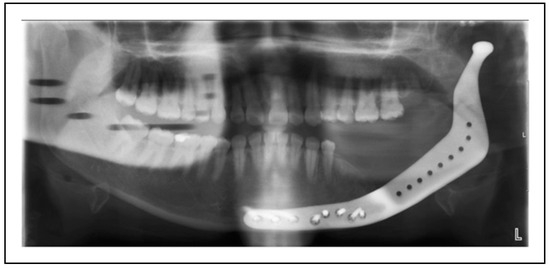

Single-Stage Regime, Patient 10